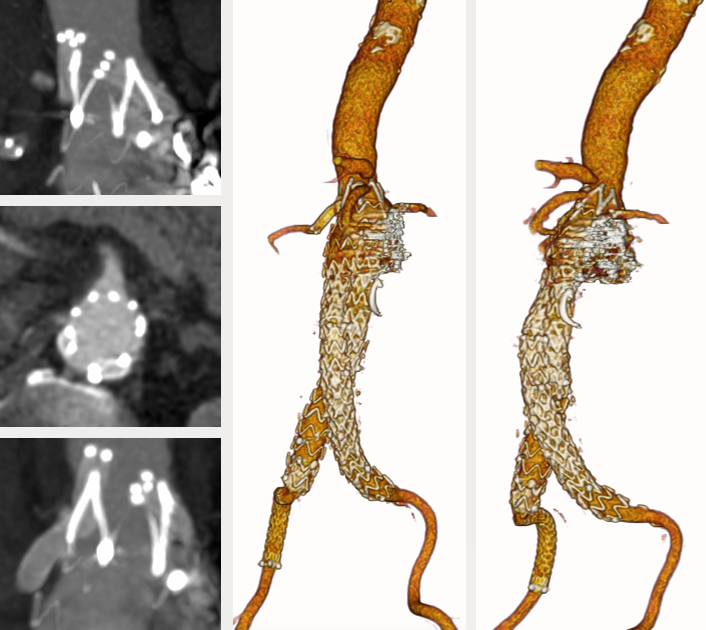

77岁男性,腹主动脉瘤EVAR后2年,再发腹痛入院。

既往:腹主动脉瘤,外院4次腔内手术史

2022年8月12日:EVAR+双肾动脉烟囱支架重建

2022年8月24日:右髂支闭塞,左髂支狭窄,右侧行Angiojet PMT,右髂支远端植入裸支架,左侧髂支中段植入裸支架,右侧保留导管CDT

2022年8月25日:右髂支血栓残余,再次PMT,右髂支中段植入裸支架

2023年3月24日:CT随访发现Ia型内漏,瘤腔弹簧圈栓塞+生物蛋白胶注射

诊断:术后CT复查Ia型内漏持续,动脉瘤2个月增大7mm

手术难点:

入路扭曲狭窄,双侧髂支多枚补救性裸支架

双肾动脉烟囱支架受裸架压迫紧贴主动脉后壁,左肾动脉烟囱支架打横

裸架丝遮挡SMA开口

弓部动脉瘤

治疗方案:PMEG拓展近端锚定区,重建CA、SMA、RRA和LRA

精准PMEG:窗口/分支无法打开,且径线缠绕,肾动脉烟囱支架挤压,弓形不适合进大鞘

容错PMEG:容错空间相对较大,对弓形和上肢入路要求低

35-14-140mm分叉型支架,缝制内分支并固定,RRA、LRA:5mm Viabahn,CA、SMA:7mm Viabahn